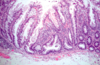

What do you see here?

- Hyperplastic polyp: BENIGN, loose, and soft

- Well-formed, elongated glands and crypts with sawtooth (star-shaped) appearance due to DEC epithelial cell turnover, delayed shedding of surface cells, and piling up of cells

- Mixture of goblet cells (with abundant mucin) and absorptive cells

- Bland cytology with eosinophilic cytoplasm

Diagnosis? Descending colon.

Hyperplastic polyp